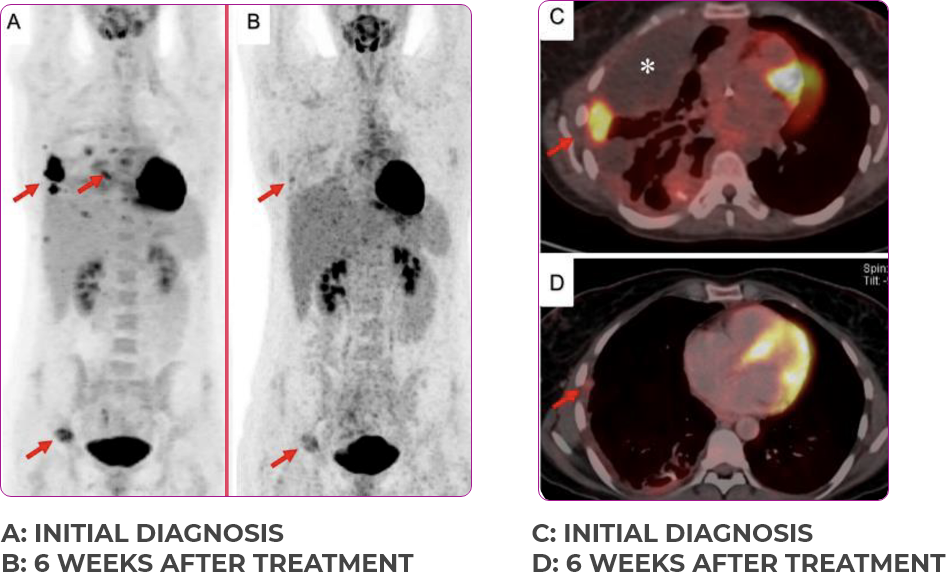

PATIENT CASE:

METASTATIC, RAIa-REFRACTORY,

PAPILLARY THYROID CANCER1,2

- 33-year-old male

- Progression on RAI and first line systemic therapy

- PRa after 2 cycles of VITRAKVI® (larotrectinib)

- Confirmed partial response on VITRAKVI lasting 55 cycles

Response to VITRAKVI1,2

- Confirmed partial response (92.6% reduction in target lesions)

- Treatment continued for 55 cycles

- VITRAKVI was well tolerated; patient did not have to discontinue due to AEa

- No treatment interruptions or dose reductions

Response in primary and metastatic lesions1

Images courtesy of Dr Steven Waguespack.